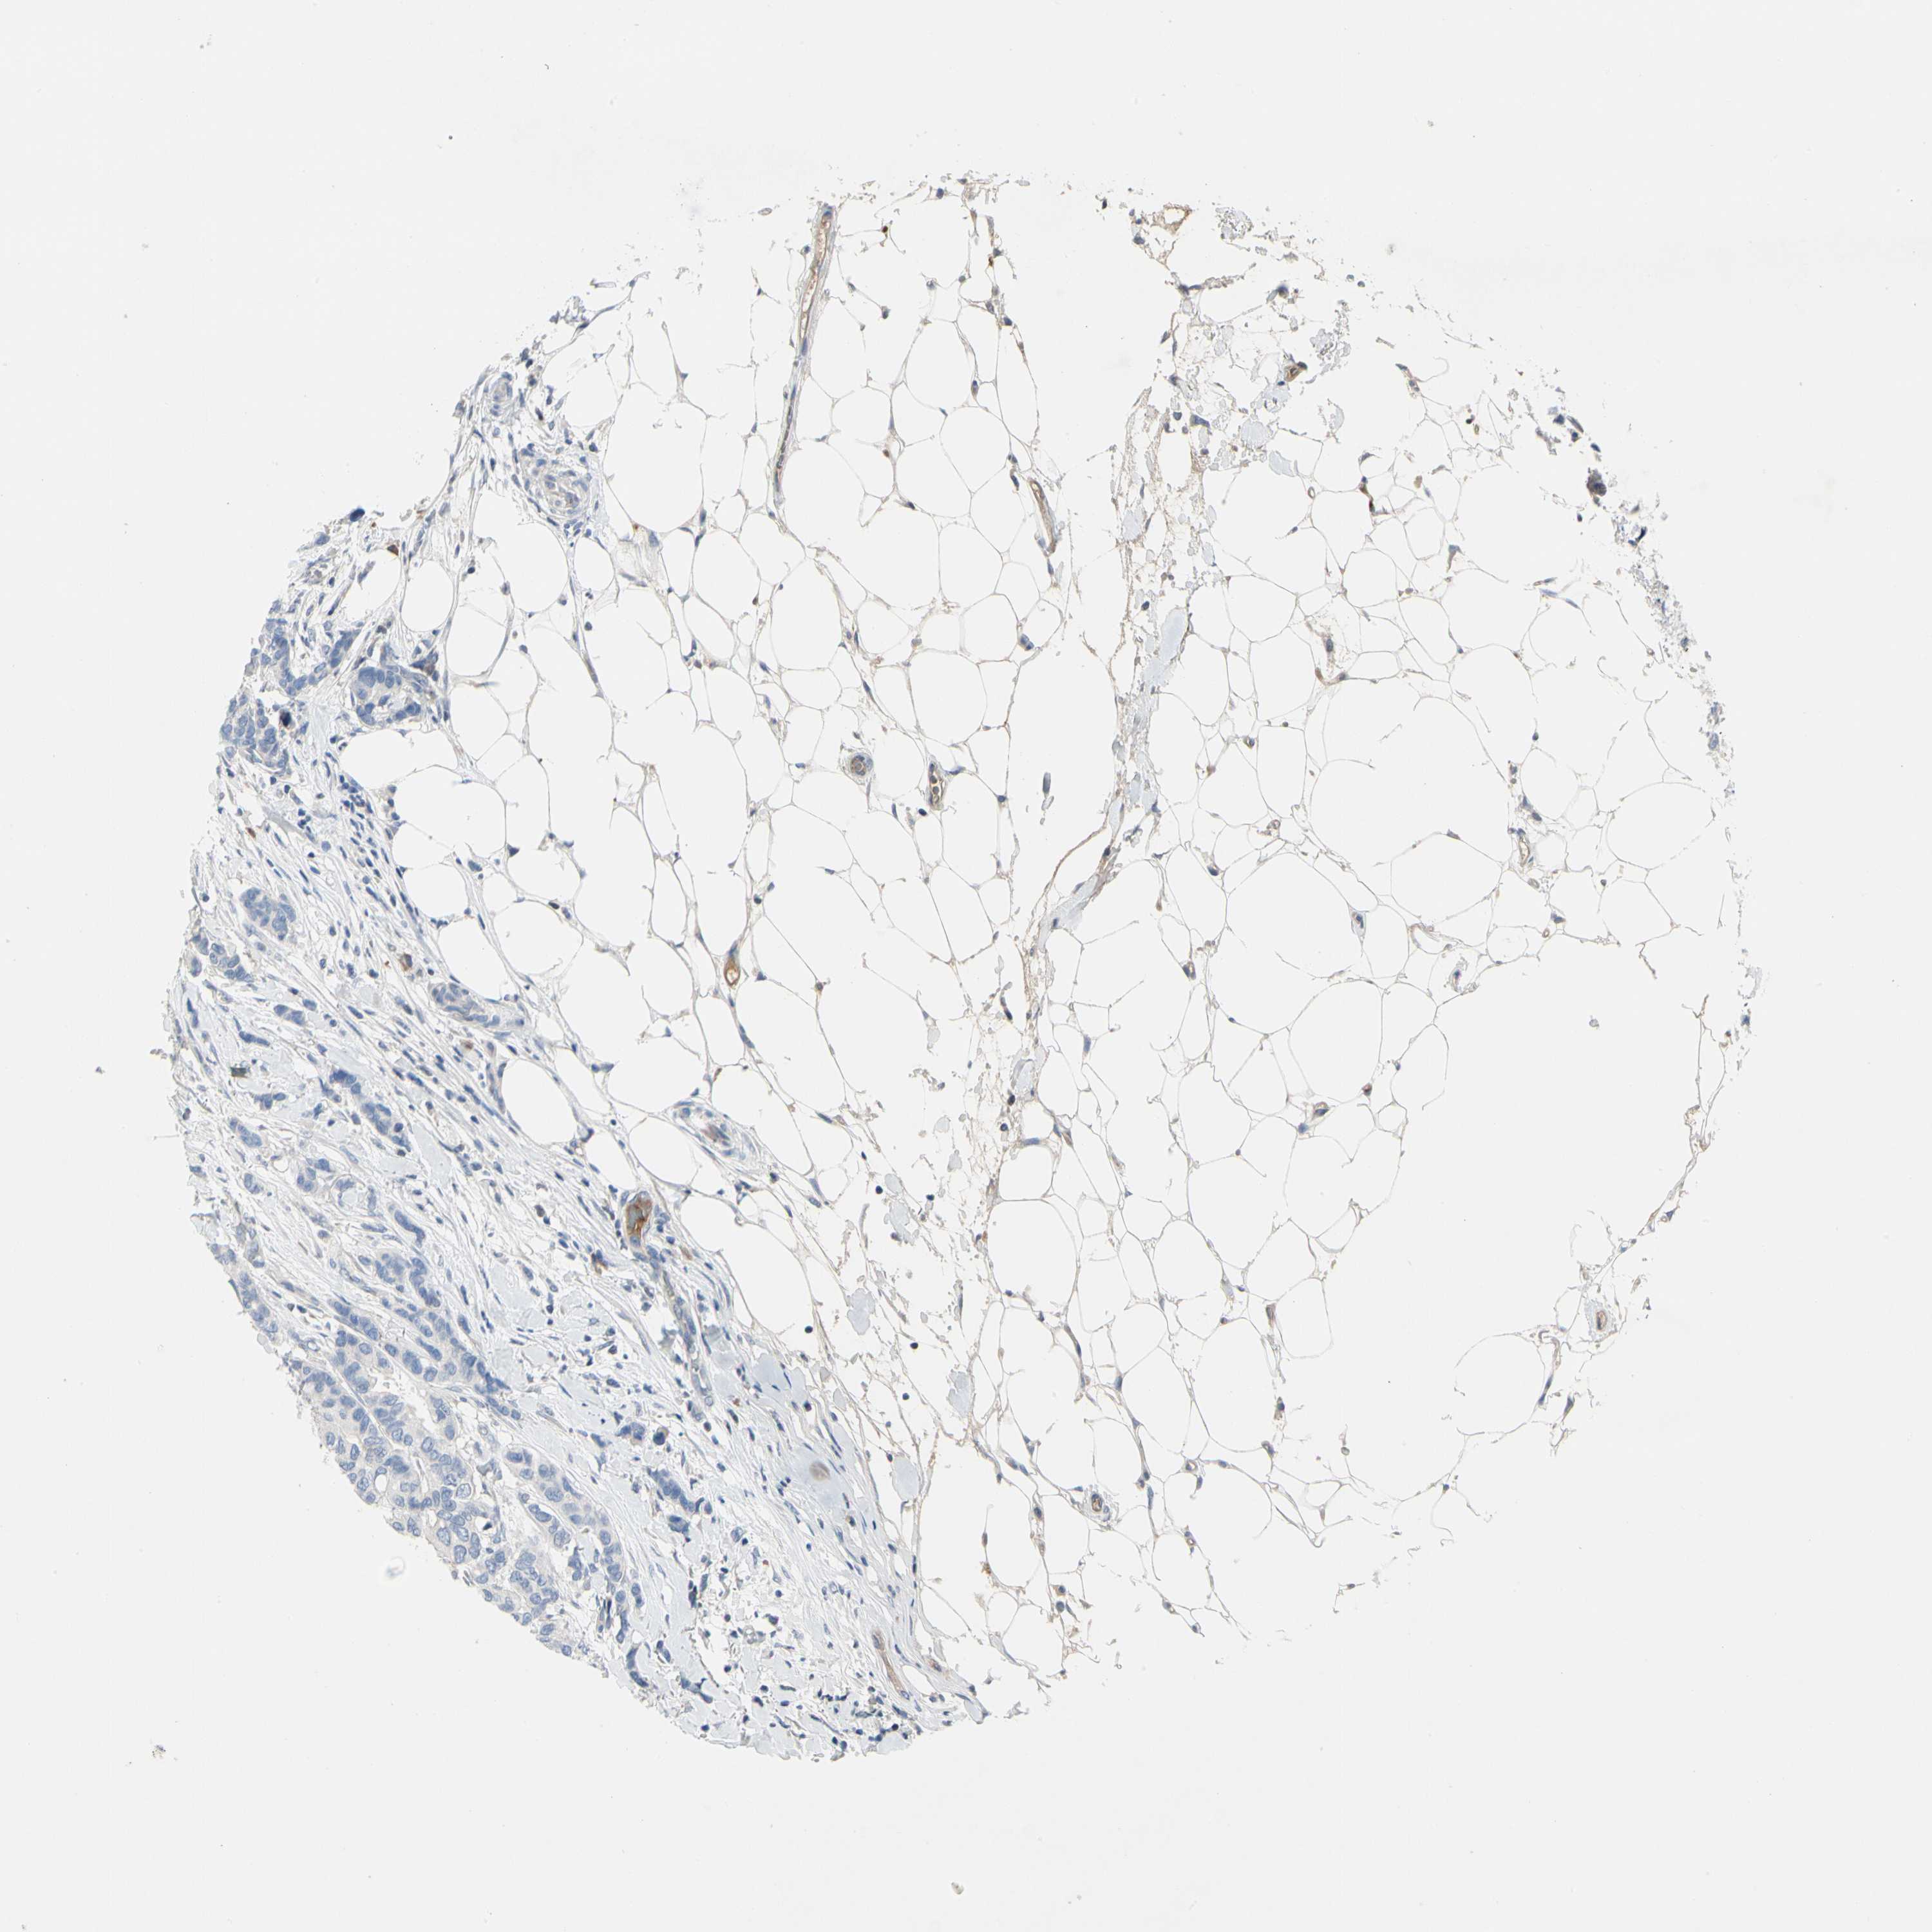

CANCER BREAST CANCER Show tissue menu

BRCA TCGA BRCA VALIDATION PROTEIN EXPRESSION